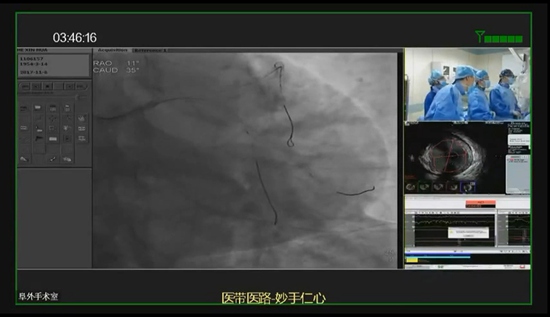

为了推动医生之间的学习交流,通过医生对医生,医生帮医生,锁定疑难重症,推进心内科手术介入治疗的不断前进,中国医学科学院阜外医院组织了医带医路学术交流系列活动。

在2017年11月8日的手术线上讨论活动中,国内心脑血管专家、阜外医院唐熠达主任进行了一场精彩的手术实操转播。而此次转播,也是科达医疗行业新品――MEDT100手术室主机的一次成功应用。